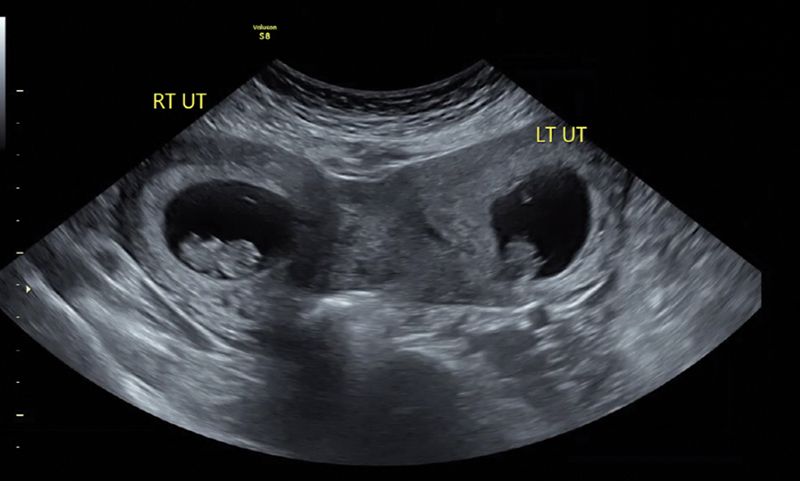

Introduction: A didelphys uterus is a rare Müllerian duct anomaly (MDA) caused by the incomplete fusion of the Müllerian ducts, leading to the formation of two distinct uterine cavities. The occurrence of simultaneous twin pregnancies, with each fetus developing in a separate horn of a didelphys uterus, is estimated at approximately 1 in 1,000,000 cases. This case report describes a rare instance of a spontaneous dichorionic diamniotic twin pregnancy, with one fetus in each horn of a didelphys uterus.

Case description: This is the case of a 35-year-old woman with unilateral renal agenesis who presented with a spontaneous dichorionic diamniotic twin pregnancy, with one fetus in each uterine cavity. This patient's pregnancy complications included intrahepatic cholestasis of pregnancy and rising creatinine levels, leading to a planned cesarean delivery at 36 weeks. The delivery was complicated by intrapartum hemorrhage and the postpartum course was further complicated by sepsis and endometritis.